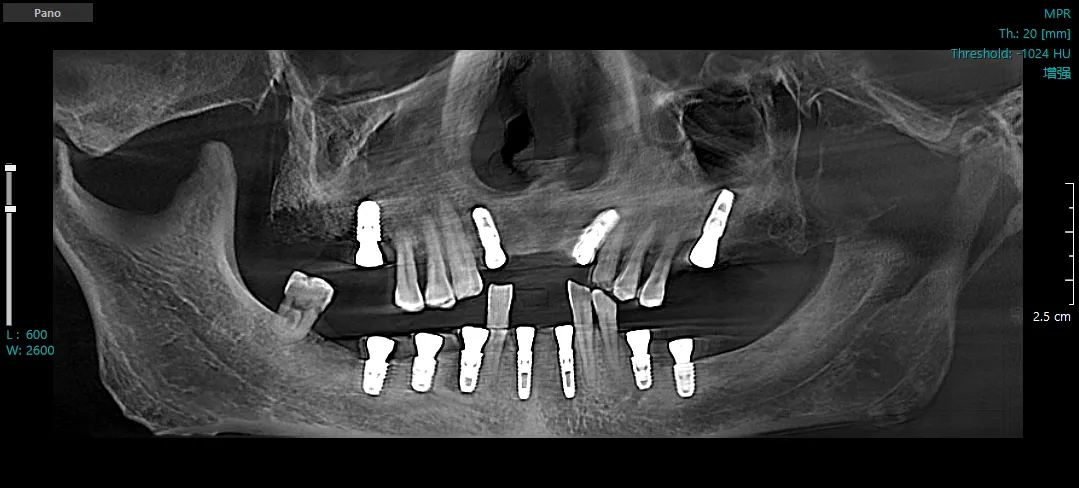

种植后CBCT三维重建图